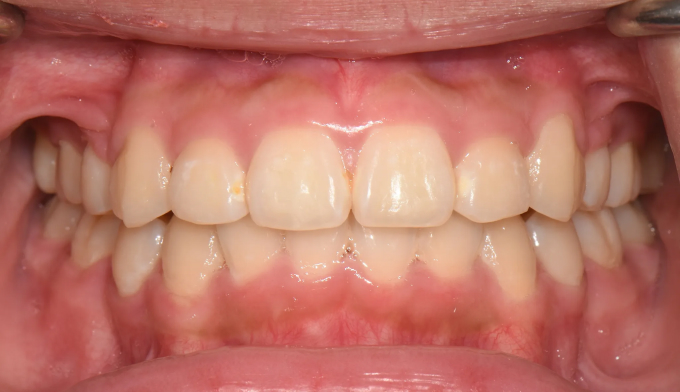

덧니

덧니가 있고, 입도 약간의 돌출감을 보입니다. 발치교정을 통해 이 모두를 해소할 수 있습니다.

치료도중, 환자 본인이 입이 너무 들어가서 얼굴 형태가 급격히 바뀌는것을 걱정하여 입을 최소한으로 집어넣기로 하였습니다. 따라서 발치 공간은 모두 치열을 가지런하는데 이용하기로 하였습니다.

발치후 교정하게 되면 교정을 위한 공간이 충분하므로 입의 전후방 위치를 마음껏 조정할 수 있다는 장점이 있습니다. 교정 중 입술의 모양이나 돌출정도를 바꾸고 싶다면 주치의에게 언제든 말씀해주세요!

교정기간은 20개월 소요되었습니다.